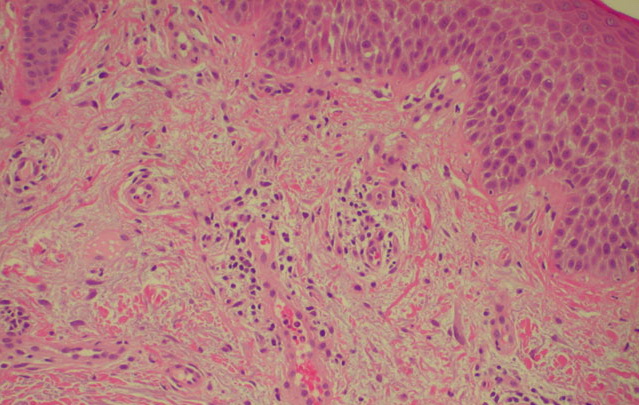

Atlas of skin histopathology